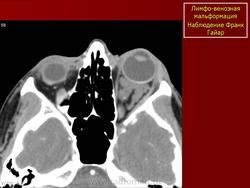

Наиболее типичная черта: выявление уровней жидкости в образовании, за счет спонтанных кровотечений.

Экстраорбитальное (но может быть рапсоалагаться как в канале, так вне его), мультикистозное, мультифокальное объемное образование с неправильным контуром.

Гиперденсное, по плотности сопоставимо с мышечной тканью, негомогенной структуры образование, пересекает анатомические границы. Стенка лимфангиомы вариабельно накапливает КВ. Тип краевого накопления КВ иногда позволяет установить умеренное ремоделирование прилежащей кости. В структуре образования иногда определяются небольшие кальцинаты или флеболиты.